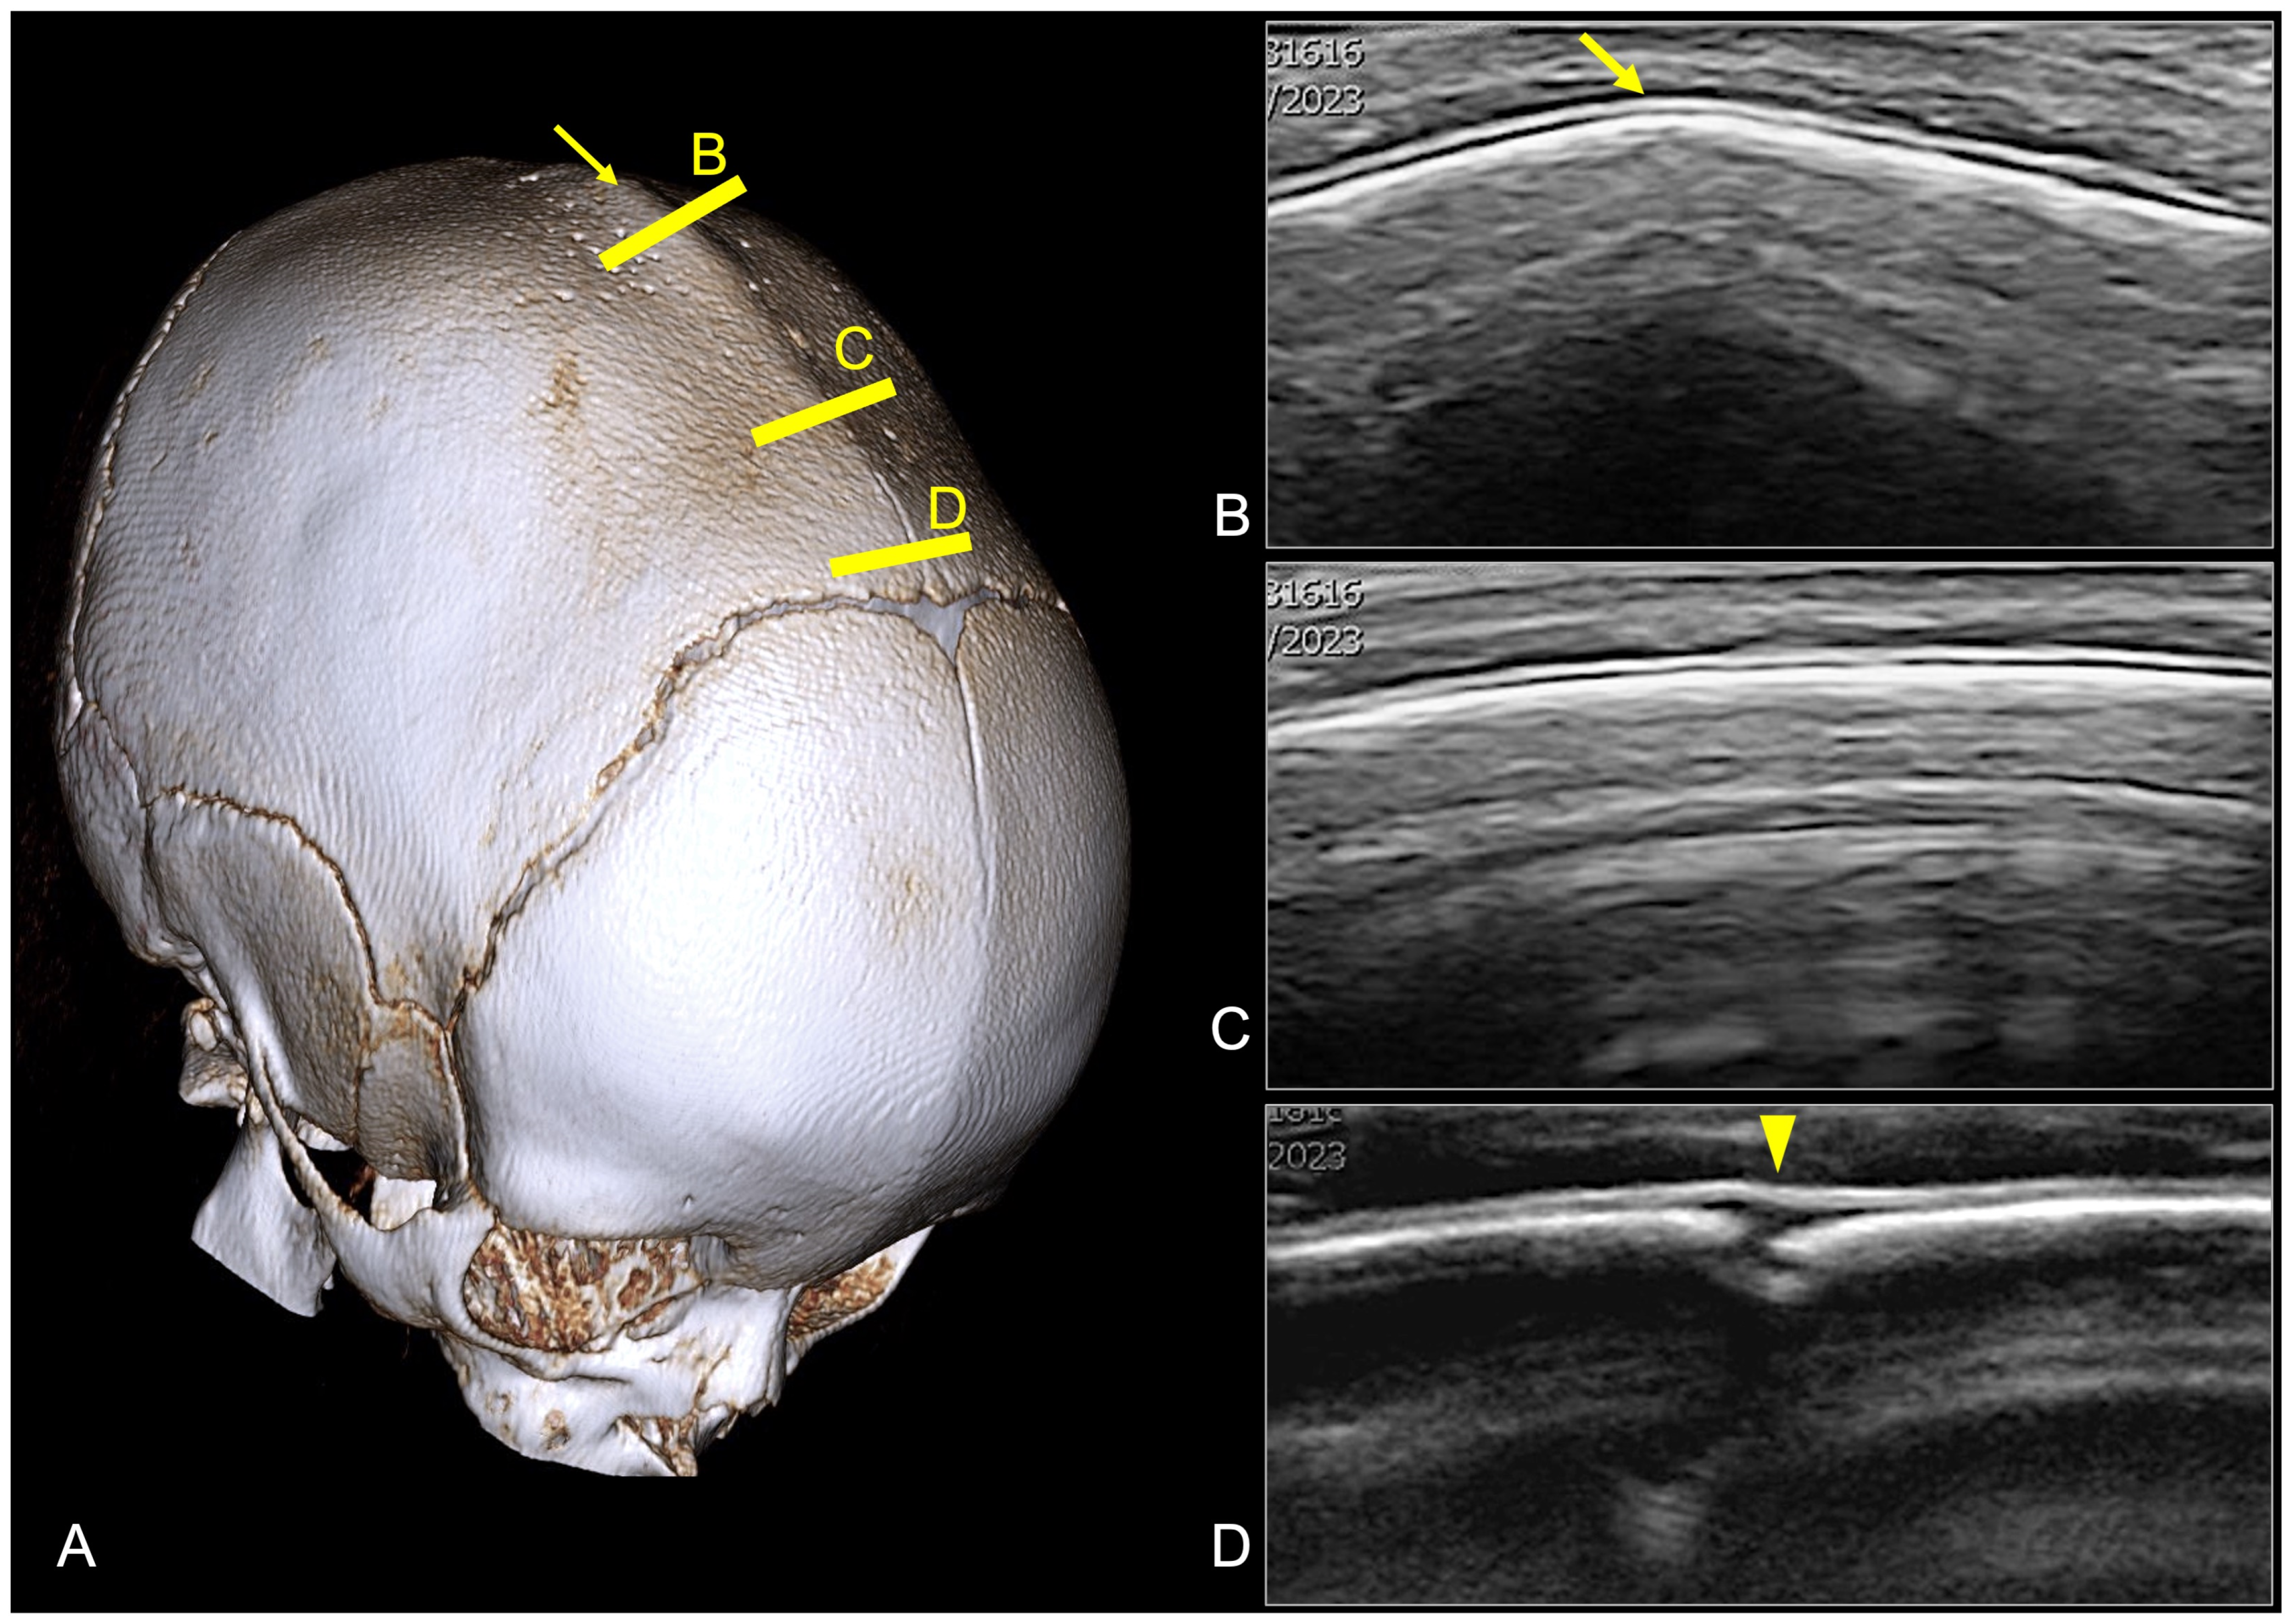

3.4. Digital Subtraction Angiography (DSA)

- Anderson, P.J.; Harkness, W.J.; Taylor, W.; Jones, B.M.; Hayward, R.D. Anomalous venous drainage in a case of non-syndromic craniosynostosis. Child’s Nerv. Syst. 1997, 13, 97–100. [Google Scholar] [CrossRef] [PubMed]

- Ghali, G.Z.; Ghali, M.G.Z.; Ghali, E.Z.; Srinivasan, V.M.; Wagner, K.M.; Rothermel, A.; Taylor, J.; Johnson, J.; Kan, P.; Lam, S.; et al. Intracranial Venous Hypertension in Craniosynostosis: Mechanistic Underpinnings and Therapeutic Implications. World Neurosurg. 2019, 127, 549–558. [Google Scholar] [CrossRef]

- Cinalli, G.; Russo, C.; Vitulli, F.; Parlato, R.S.; Spennato, P.; Imperato, A.; Quarantelli, M.; Covelli, E.; Aliberti, F. Changes in venous drainage after posterior cranial vault distraction and foramen magnum decompression in syndromic craniosynostosis. J. Neurosurg. Pediatr. 2022, 30, 330–341. [Google Scholar] [CrossRef]